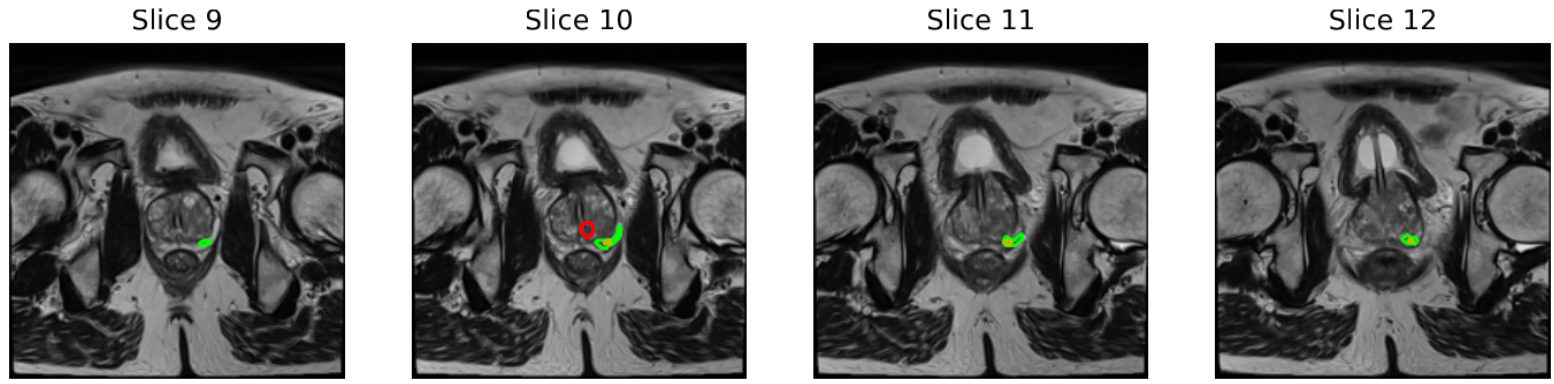

Human-alone ¡ AI. The workflow of Study 1 allows us to compare the baseline performance of humans and AI on the same set of patient cases. As shown in Table 1, AI consistently outperforms humans across most metrics, with statistically significant advantages in AUROC, accuracy, specificity, and PPV/precision(p<0.05p<0.05). At the lesion level, the AI also shows significant gains in accuracy, sensitivity, and PPV. Moreover, we find that for identified positive lesions, AI is less likely to miss the biopsy confirmed lesions, compared with human radiologists. Fig. 3 provides an example of this. These findings suggest that the AI is better than human radiologists in predicting csPCa, especially in identifying true negative cases and true positive lesions.

Refer to caption

Figure 3. An example of lesion-level annotation comparing human experts (red contour), AI (yellow contour), and expert annotation from the dataset (green contour). In this case, the AI successfully detected a lesion which corresponded to a clinically significant prostate cancer in the dataset; our human radiologist did not identify this lesion, and instead annotated a lesion in the transition zone.